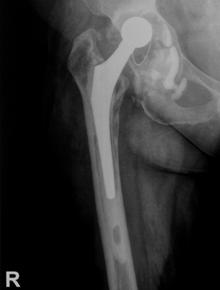

In cadrul procesului de strangere a datelor in vederea includerii pacientilor in prezenta lucrare am putut analiza foile de observatie si investigatiile imagistice efectuate in vederea diagnosticarii patologiei si verificarii succesului terapeutic. Cu aceasta ocazie am putut observa zonele in care decimentarea s-a produs si s-a luat decizia construirii unui tabel de frecvente in vederea compararii pattern-ului de decimentare constatat la pacientii inclusi in prezenta lucrare cu rezultatele din literatura.

Avand in vedere faptul ca radiografia in incidenta postero-anterioara a fost realizata in cazul tuturor pacientilor, am decis ca zonele Gruen de decimentare analizate sa fie 1-7. In Tabelul nr. 2.2.3 sunt prezentate zonele Gruen de decimentare 1-7 si frecventa lor in cadrul lotului de studiu.

Spre deosebire de datele din literatura, care indica mai ales linii de decimentare la nivelul zonelor Gruen 1 si 7, in cazul pacientilor inclusi in actuala lucrare se constata atat decimentari in zonele 1 si 7 dar si in zonele 2, 3, 5 si 6 cu o frecventa mai mare decat cea intalnita in datele disponibile.

Decimentarile din zonele 1 si 7 au fost intalnite cel mai frecvent in analiza radiografiilor, fiind observate in 72%, respectiv 78% din cazuri. In cate 44% din cazuri au fost observate linii radiotransparente in zonele 2, respectiv 5, iar pe radiografiile a 53% dintre pacienti a fost observata o linie de decimentare in zona Gruen 6.

Aceste observatii nu se coreleaza [27] cu datele intalnite care relateaza decimentari in zonele Gruen 2-6 in aproximativ 1% din cazuri.